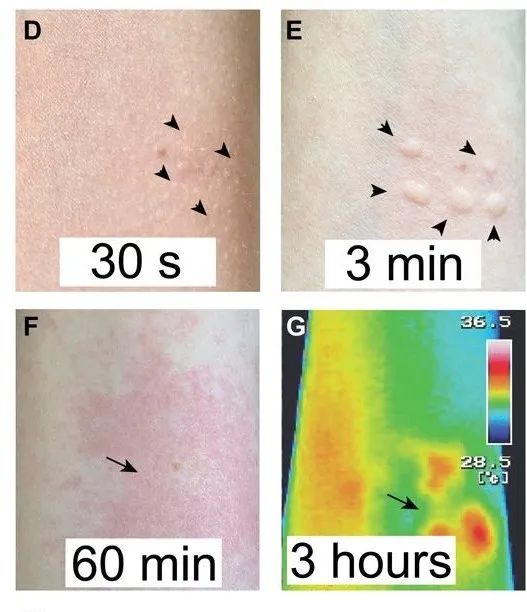

接触金皮树后皮肤随时间的反应。图片来源:(DOI)10.1126/sciadv.abb8828